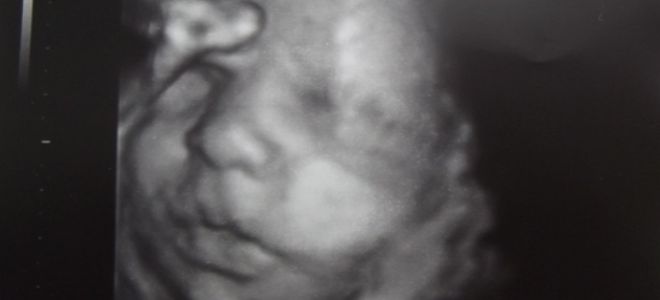

Как выглядит ребенок на 36 неделе беременности?

На 36-й неделе беременности плод приобретает окончательный внешний вид. В этот период изменения происходят минимально. Щеки малыша начинают округляться, что характерно для всех новорожденных. Кожа становится гладкой, мелкие складочки исчезают. Объем первородной смазки уменьшается, что также приводит к снижению количества околоплодных вод.

Надбровные дуги становятся четко видимыми, на них появляются волоски (брови). Ресницы также начинают формироваться. Голова малыша покрыта короткими волосами, которые уже имеют пигментацию (на цветном УЗИ можно увидеть, какого цвета волосы у ребенка). Хрящи, формирующие ушные раковины, становятся более плотными, и уши выглядят как у взрослого, но меньшего размера.